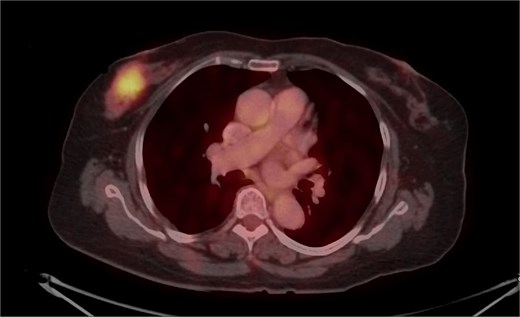

Mammography revealed an asymmetrical density in the upper outer quadrant of the right breast with BIRADS V classification. Ultrasonography identified an irregular hypoechoic lesion measuring 3.8 × 2.5 cm in the right breast. Additionally, multiple enlarged axillary lymph nodes with cortical thickening were seen, the largest measuring 1.02 cm in diameter. A core needle biopsy of the breast lesion demonstrated features of invasive carcinoma, not otherwise specified (NOS), Grade II based on the Nottingham grading system. Immunohistochemistry revealed the tumor to be ER-positive (78%), PR-negative, Her2Neu-negative, and Ki67–21%, confirming it as Luminal A subtype. The excised axillary lymph nodes exhibited caseating granulomatous inflammation, consistent with tuberculosis (Fig. 1). Acid-fast bacilli (AFB) testing further confirmed the diagnosis of TB. Pre-surgical imaging revealed metabolically active areas in the breast lesion and axillary lymph nodes with no evidence of systemic metastases (Figs 2 and 3).

PET-CT axial view of the thorax, indicating a metabolically active lesion in the right breast.